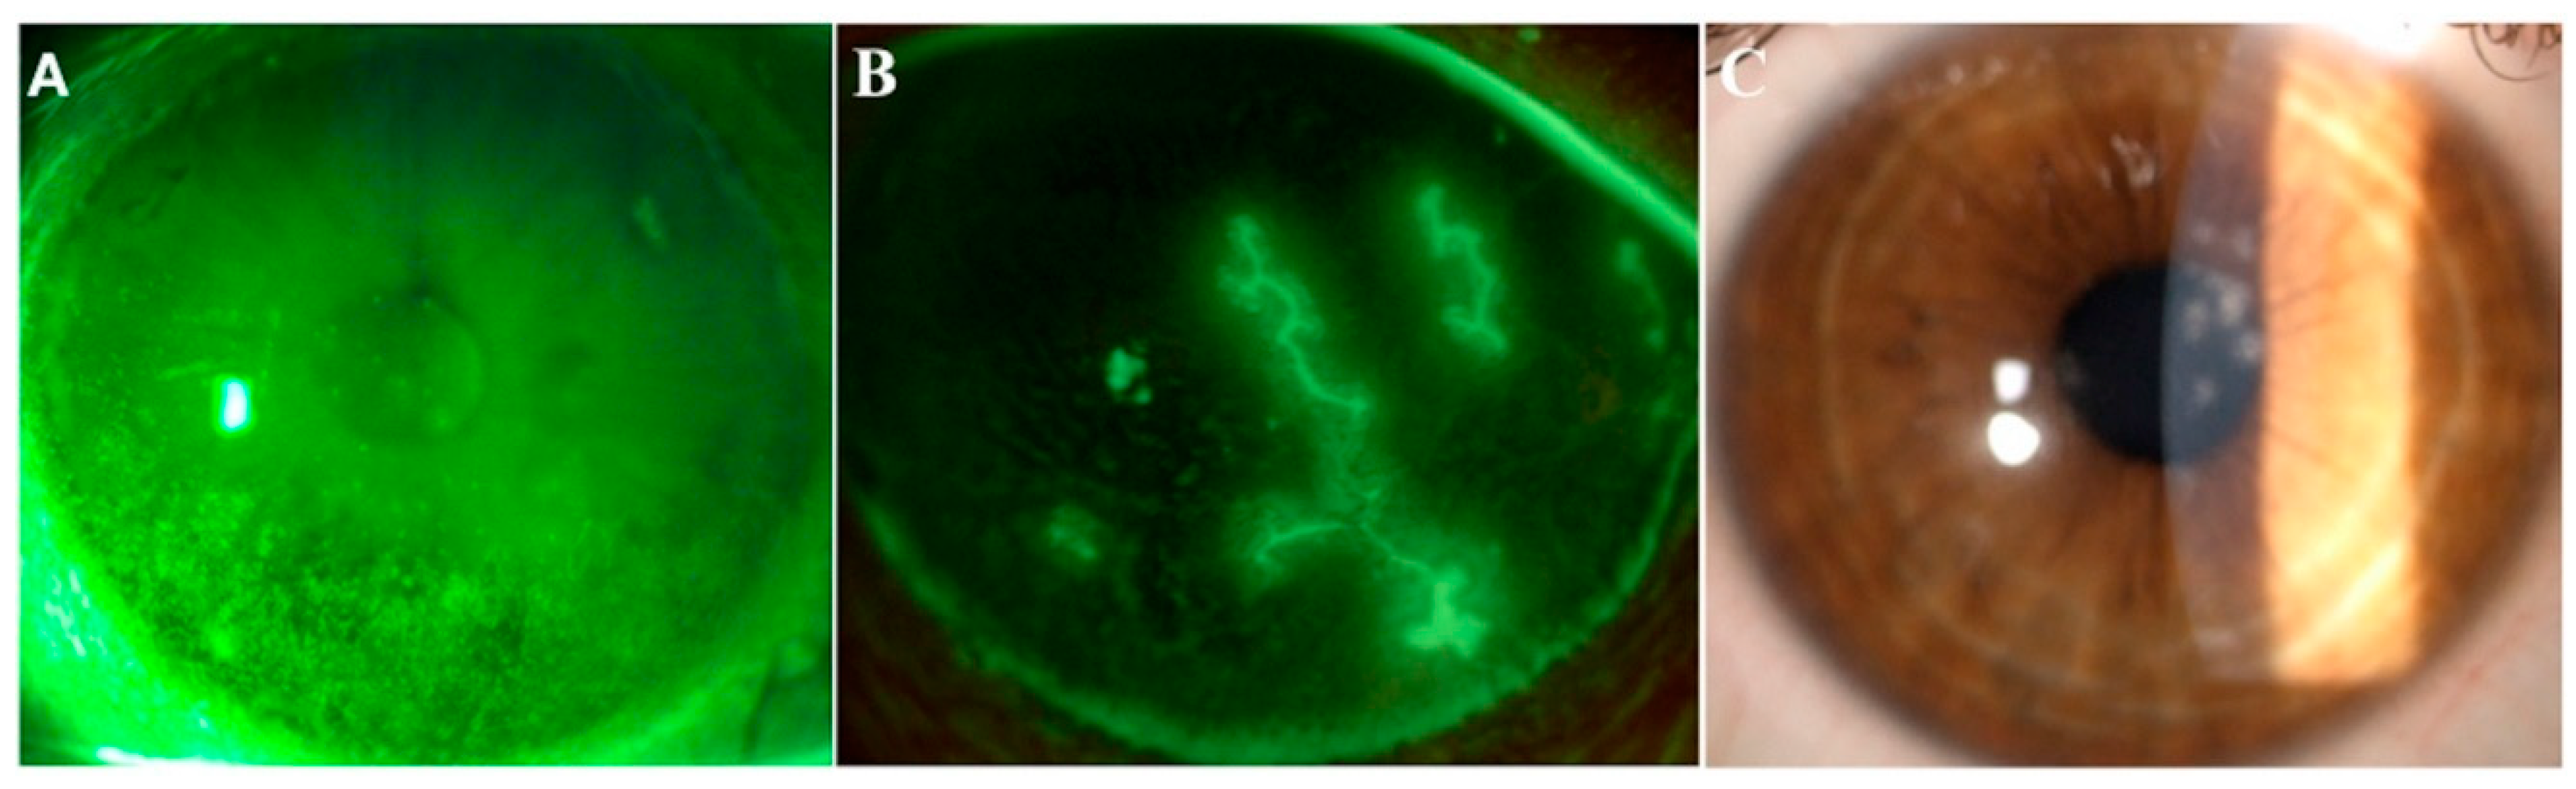

Figure 2.

Images from three representative patients affected by dry eye, herpetic keratitis and adenoviral keratoconjunctivitis. Representative images of ocular conditions that may benefit from the use of lactoferrin: dry eye (A), herpetic keratitis (B) and epidemic keratoconjunctivitis (C). (a) Slit lamp photograph of the cornea of a patient with dry eye after the instillation of 20 μL of unpreserved 2% sodium fluorescein and use of the yellow filter to enhance the staining details. The epithelial damage is visible with fluorescein staining as multiple punctate epithelial erosions scattered over the corneal surface, in particular in the lower sectors. (b) Slit lamp photograph of the cornea of a patient with herpetic keratitis after the instillation of 20 μL of unpreserved 2% sodium fluorescein and use of the yellow filter to enhance the staining details. Classical dendritic epithelial defects are visible with positive fluorescein staining. (c) Slit lamp photograph of a patient with adenoviral conjunctivitis showing multifocal sub-epithelial (stromal) corneal infiltrates.

Topical application of lactoferrin has been shown to reduce irradiation-induced corneal epithelial damage in mice models, as well as to promote corneal wound healing after alkali-burn injury [16,17]. Furthermore, previous studies have reported a significant correlation between low levels of tear lactoferrin and the development of both dry eye disease (DED) and chronic meibomitis [18,19,20] (Figure 2A). These two common disorders of the ocular surface system share a degree of mutual pathophysiology, since markers of inflammation and oxidative stress are present in both conditions [21]. Indeed, a decreased volume and an altered qualitative composition of tear film, together with excessive tear evaporation, lead to the creation of a hyperosmolar environment, which then initiates both inflammatory and oxidative cascades, resulting in impaired epithelial proliferation and differentiation [22]. The rationale of the use of lactoferrin in the setting of DED derives from its capacity to directly address the vicious cycle of the disease, especially the underlying inflammation and oxidative stress. In particular, thanks to its iron-chelating ability, lactoferrin provides oxygen free radical and hydroxyl scavenging activities, thus inhibiting pro-inflammatory and tissue damaging effects of reactive oxygen species (ROS). On the other hand, lactoferrin attenuates excessive inflammation in host responses to pathogens by inhibiting classical complement activation and by downregulating inflammatory mediators such as tumor necrosis factor (TNF)-alpha, interleukins (ILs)-1, -6 and -8, the intercellular adhesion molecule (ICAM)-1 and CD14 [23] (Figure 1). In a study by Dogru et al., patients supplemented with oral lactoferrin showed ameliorated dry eye symptoms and tear film stability [24]; another study reported its efficacy in improving ocular surface parameters, such as tear break-up time and the Schirmer test, in patients affected by dry eye induced by cataract surgery [25]. Furthermore, locally applied lactoferrin was able to restore corneal epithelial integrity in a rabbit model of dry eye, suggesting the potential use of lactoferrin eye drops for treating DED [26].

By adopting similar mechanisms, lactoferrin may address adenovirus, which is the main causative factor of epidemic keratoconjunctivitis (Figure 2C).

This is a highly contagious condition associated with marked inflammation, conjunctival hyperemia and edema, and symptoms of irritation, tearing, blurry vision and light sensitivity. Its inappropriate diagnosis and treatment may lead to the development of pseudomembranous conjunctivitis, with resultant scarring and symblepharon formation, which alter the local homeostatic balance contributing to the onset of a vicious circle of ocular surface disease.